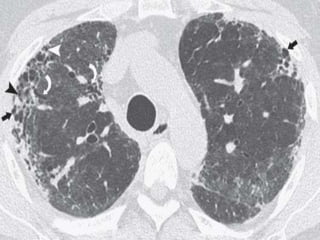

3. Patchy involvement- Areas of mild and severe

fibrosis and normal lung are often present in

the same patient, in the same lung, and in the

same lobe.

 A confident diagnosis of IPF on HRCT requires clinical

exclusion of known causes of UIP and the presence of all of

the following four criteria: reticular pattern, honeycombing,

subpleural and basal predominance, and absence of atypical

features.